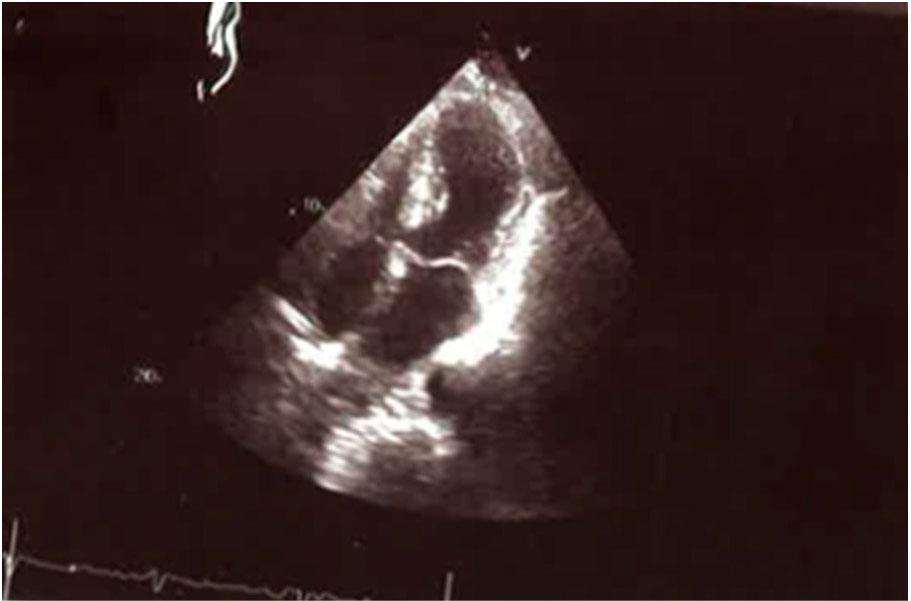

Figure 1.